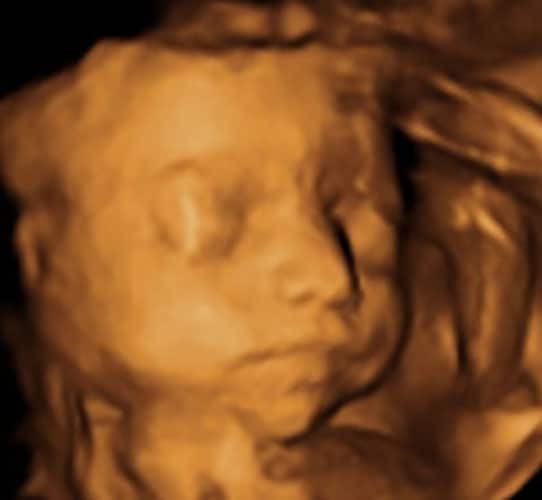

Ultraschallbilder aus dem 3. Trimester (29. bis 40. SSW)

Im dritten Trimester der Schwangerschaft ist das Baby so groß, dass es nicht mehr komplett auf ein Ultraschallbild passt. Nun kann man wunderbare 3D-Ultraschalle des Gesichts machen. In diesem Semester nehmen die Babys nochmal rasant zu und wer Glück hat, kann auf seinem Ultraschall schon erste Gesichtszüge erkennen.

Was genau man auf einem Ultraschallbild erkennen kann, hängt nicht nur von der Größe des Babys ab, sondern auch davon wie gut das Ultraschall-Gerät ist, mit dem die Aufnahme gemacht wurde. Auch auf den Ultraschallbildern hier kannst du sehen, dass die Qualität stark schwankt. In der Regel kann man gut den Kopf und RUmpf des Babys erkennen und auch die Gliedmaßen erkennt man selbst als Laie gut.

Wer sich jedoch erhofft Gesichtszüge zu erkennen, der wird oft enttäuscht. Zwar kann man beim 3D-Ultraschall schon eine Menge sehen, aber das umgebende Fruchtwasser sorgt in den allermeisten Fällen für starke Störungen.